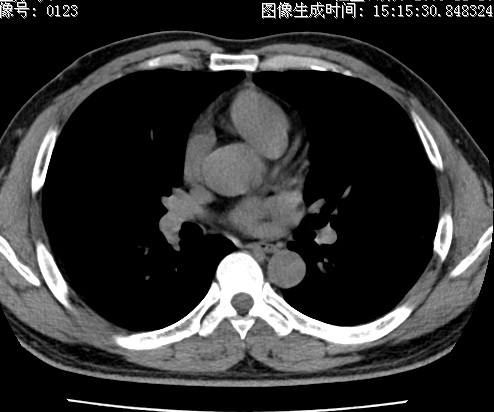

以下是引用zhao_bin2008在2010-1-4 20:15:00的发言:[br]先天性肺囊肿或小的肺隔离症?

以下是引用卜一在2010-1-4 22:09:00的发言:[br]先天性肺囊肿或小的肺隔离症?支持!

以下是引用zsl6918在2010-1-5 5:23:00的发言:[br]良性改变!肺囊肿,先天性支气管闭锁,血管畸形等均有可能。

以下是引用影像之路在2010-1-6 11:10:00的发言:[br]腺癌,最终的病检有些出乎意料之外,术前同志们大多考虑为肺囊肿或小的肺隔离征 [br]回过头来看 小结节呈分叶状,其内侧有一条较粗的静脉供血或许能成为支持诊断腺癌的理由